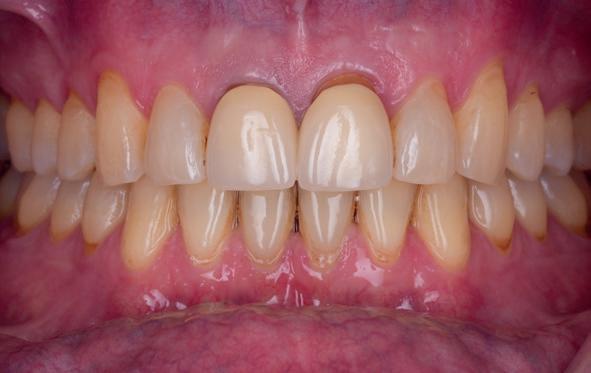

• Intra-orale scan voor studiemodellen, proefopstelling en beoordelen ruimte palatinaal

Vervaardigen essix retainer met dummies waarbij er een emergence profile van de 11 en 21 werd gevormd door eivormige dummies 4 mm in de gingiva te plaatsen

• Aanvulling zachte weefsels met de VISTA techniek en een vrij gingivatransplantaat uit het palatum links en direct dragen van de essix retainer

Na 4 weken intra-orale scan voor de etsbrug en kleurbepaling bij de technicus

• Plaatsen van de etsbrug met een composietcement

Voordat er gescand kon worden voor een etsbrug, werd een studiemodel vervaardigd om met de technicus te overleggen of er voldoende ruimte was voor 2 centrale incisieven in de mesio-distale zin en of er voldoende ruimte was in occlusie voor de vleugels van de etsbrug. Er hoeft enkel nog aan de 12 en 22 pala-

tinaal geslepen te worden als er geen 1,5 mm ruimte voor de vleugels behaald kan worden. De ruimte was op de dunste plekken 1 mm, dus een kleine preparatie in de 12 en 22 palatinaal was nodig. Omdat de kaak volledig afgevlakt was en dun was geworden, kunnen de dummies van de etsbrug enkel op de kaak “gelegd worden”, maar daarbij zijn er geen papillen en staat de cervicale rand van de dummies net voor de kaak. Een esthetisch resultaat kan daarmee niet behaald worden. Daarom is een aanvulling van de zachte weefsels in de breedte nodig, als het creëren van een emergence profile, waarbij het oogst alsof de gebitselementen uit het weefsel vertrekken.

Voor de aanvulling zachte weefsels chirurgie werd gekozen voor de VISTA techniek, hierbij worden er twee incisies partial thickness flap hoog in de mucosa gemaakt, waarna er ruimte vanuit de incisies wordt getunneld tussen de gingiva en het periost door middel van VISTA tunnel instrumenten. Uit het palatum links werd een vrij gingivatransplantaat geoogst van 15x10 mm met een dikte van 3 mm, die voor inhechten werd geëpithelialiseerd. Als het epitheel niet wordt verwijderd, kan deze graft door

de mucosa heen groeien, dat ten koste gaat van de esthetiek. In het donorgebied wordt een collageen spons ingehecht, waardoor de patiënt daar minder last van heeft. Het bindweefsel wordt door de hul-

pincisies met hechtingen naar het buccale en coronale deel getrokken en aldaar ingehecht. Met twee incisies werd ook de emergence profile gecreëerd (afbeelding 6-13). Voor een goede genezing van het

5. Beginsituatie voor behandeling

6. VISTA techniek twee hulp incisies

7. Vervaardiging tunnel met tunnelinstrumenten

8. Geoogst bindweefseltransplantaat uit palatum

9. Na de-epithelialiseren van transplantaat

10. Inhechten van een collageenspons in het donorgebied

11. Middels hechtingen het op de juiste plek trekken van het transplantaat

12. Transplantaat ingehecht

13. Occlusaal beeld verdikking van de zachte weefsels

14. Direct postoperatief plaatsen

van de essix met 2 dummy tanden

15. Twee weken post operatief

16. Creëren van een duidelijke indeuking in de mucosa voor emergence profile

17. Genezing van het palatum

18. Etsbrug frontbeeld

19. Etsbrug palatinaal